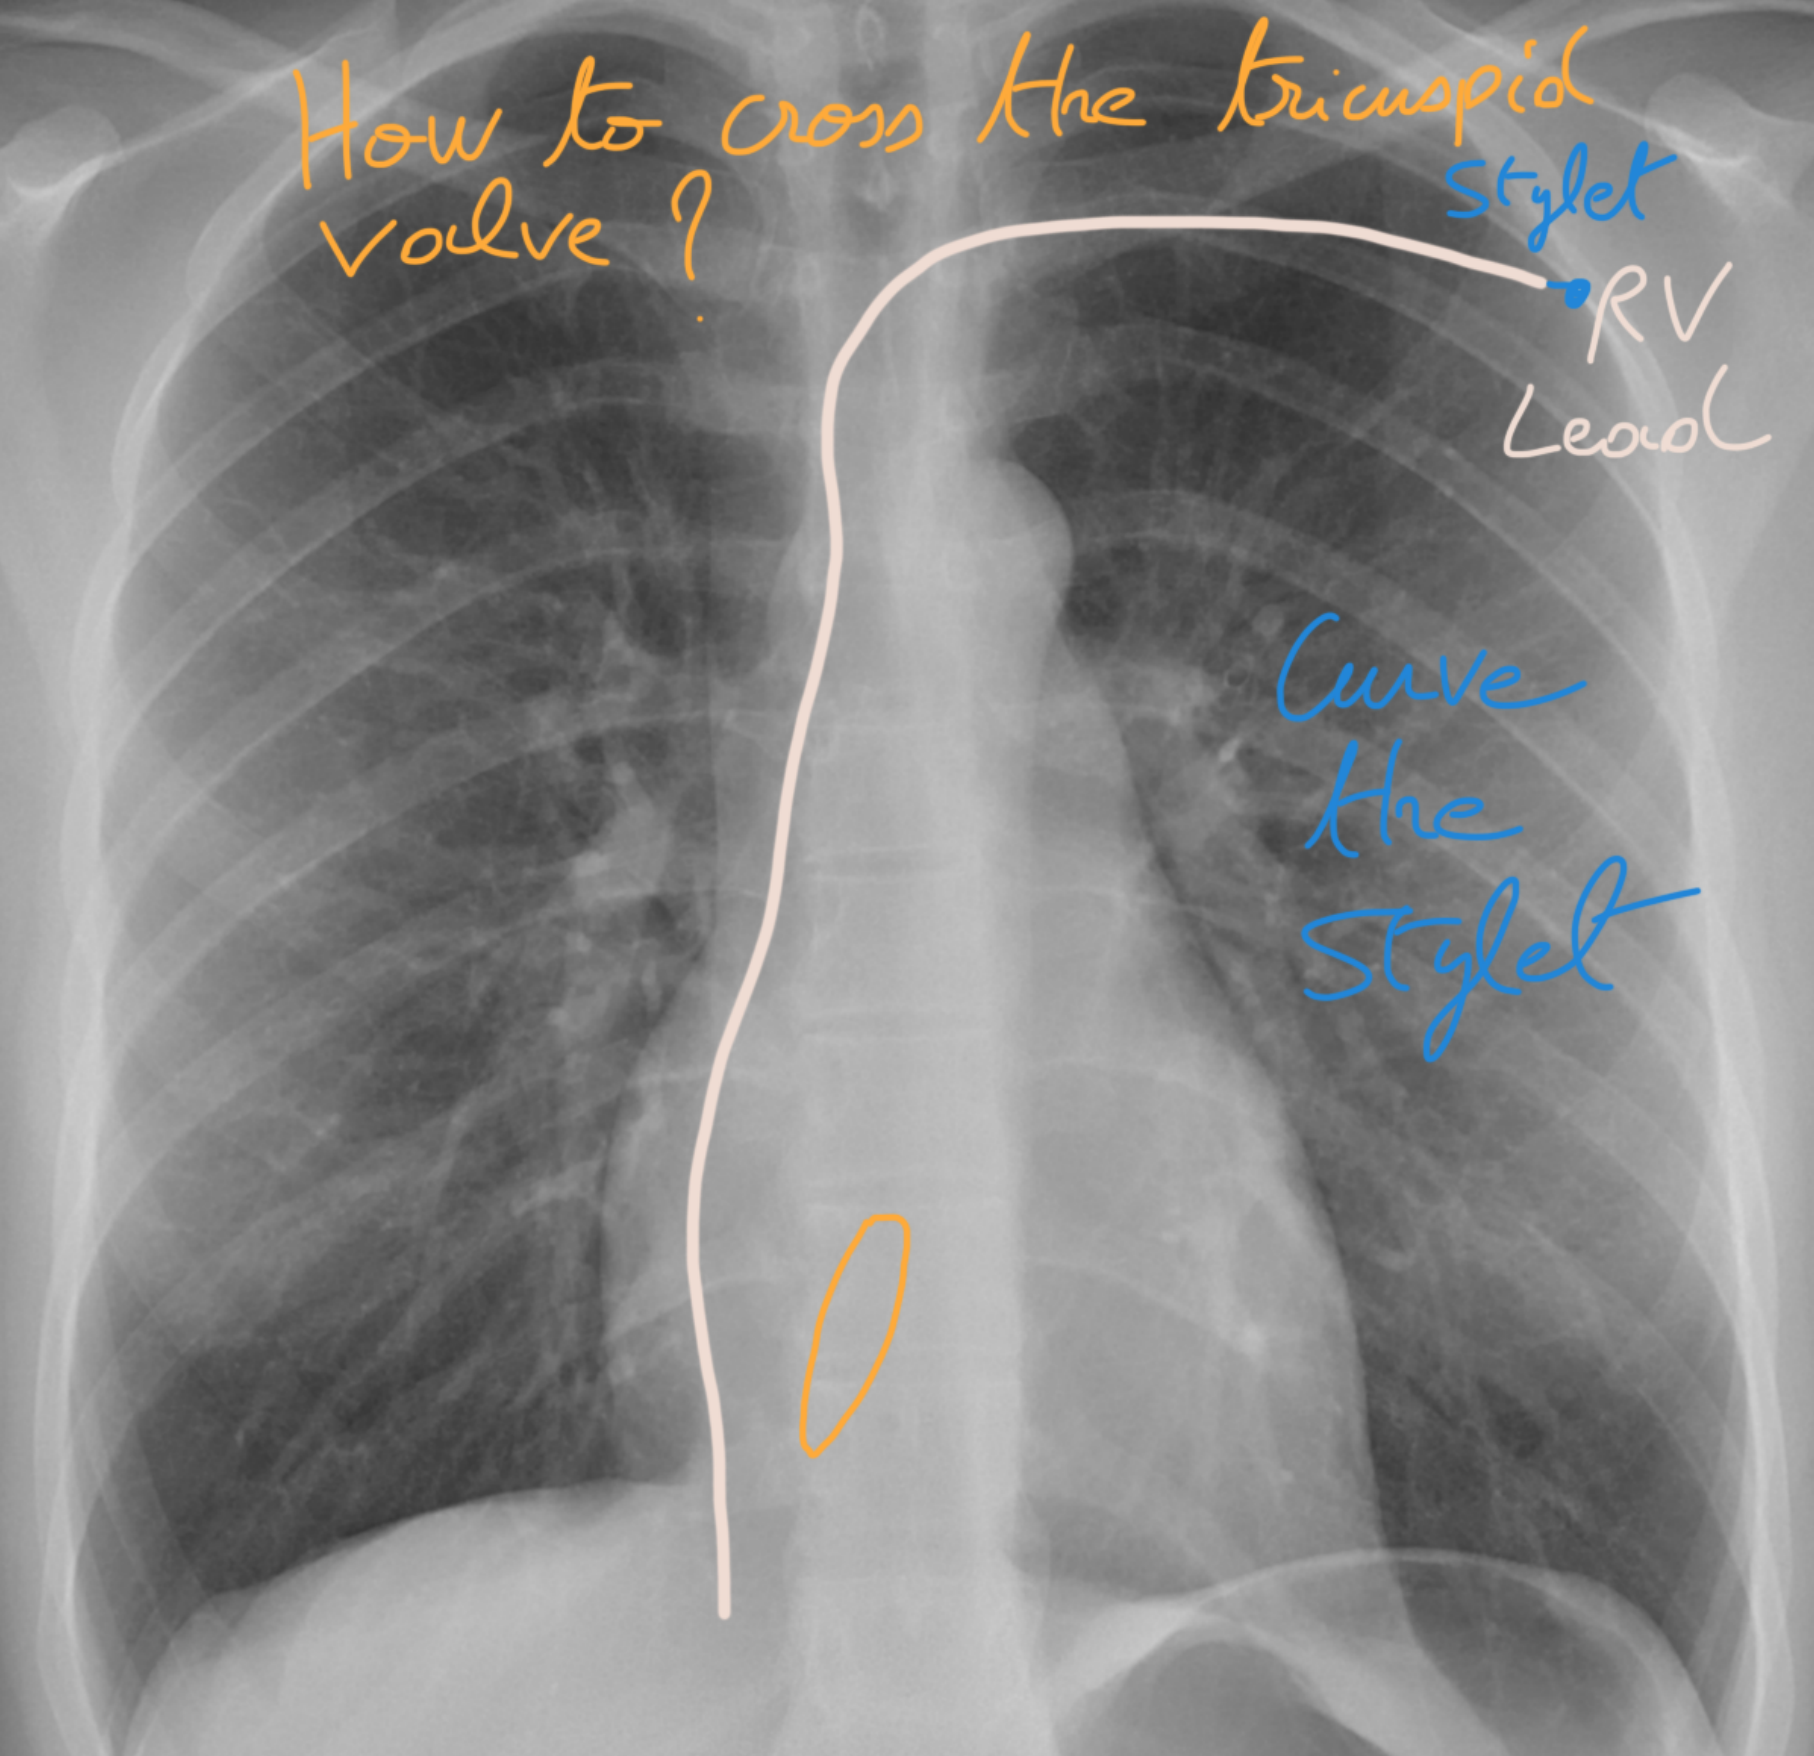

๐Ÿ”„ Step 15: How to cross the tricuspid valve! ๐Ÿซ€๐Ÿšช

Use the stylet and shape it with two curves:

1๏ธโƒฃ The first curve along the shaft

2๏ธโƒฃ The second curve at the tip, like in the 3D diagram ๐ŸŒ€

๐Ÿ‘‰ Think of it like threading a key through a tricky lock ๐Ÿ”‘ โ€” precise curves make all the difference!

๐ŸŒ€ Step 16: Securely cross the tricuspid valve! ๐Ÿšช๐Ÿ’ช

This special stylet curvature lets you safely pass through the tricuspid valve.